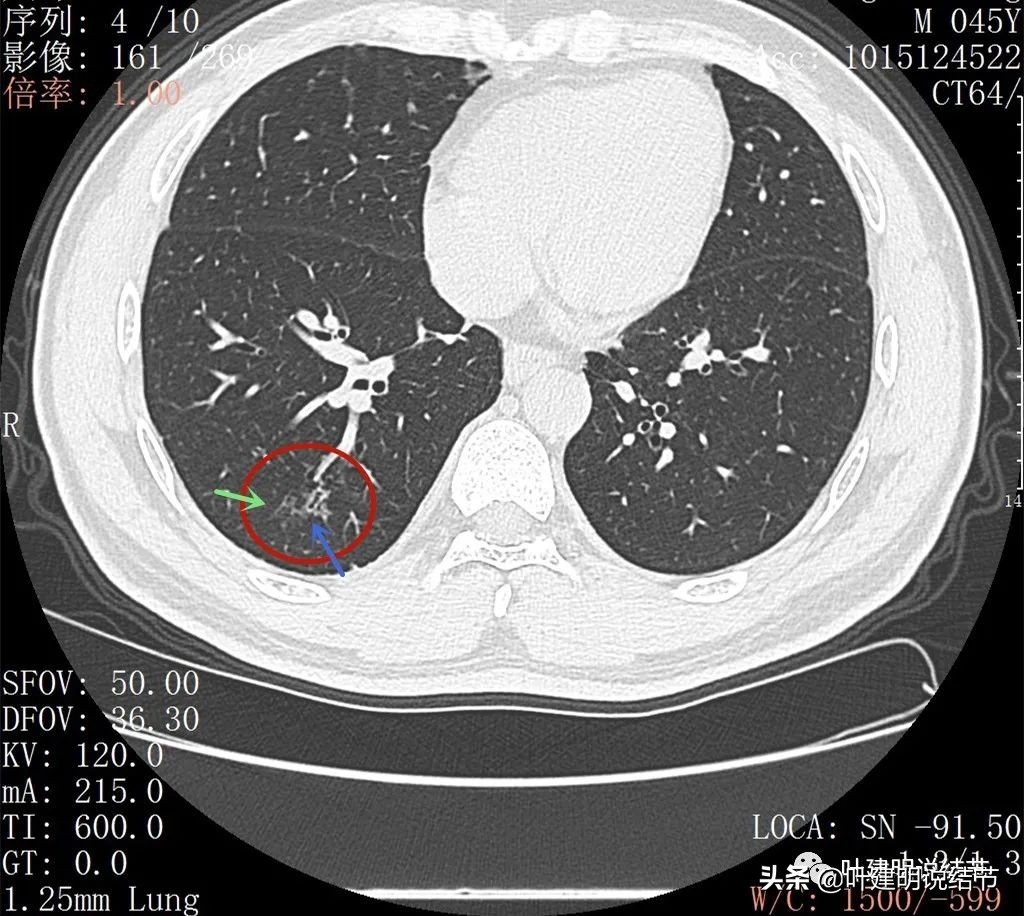

2022年5月复查靶扫描的图像:

病灶出现,磨玻璃密度,非圆形或类圆形,感觉比较散

病灶虽然不密,但轮廓较清,磨玻璃成分明显,感觉偏向恶性

病灶有少许实性成分(粉色箭头)

病灶似有血管进入(桔色箭头),而且血管异常增粗,整体病灶轮廓较清,似有分叶,中间有空泡征呈蜂窝状

病灶内部见血管穿行,轮廓与瘤肺边界清楚

扩张的细支气管感觉较为僵硬

少许区域有密度较高的部分,扩张细支气管明显,且显僵硬